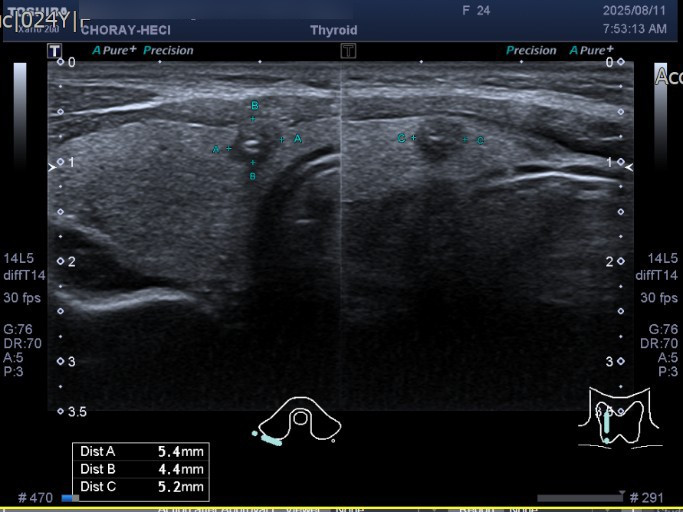

Thùy phải nhân echo kém đặc # 5.4*4.4*5.2 mm, trục ngang, vôi hóa thô, bờ không đều